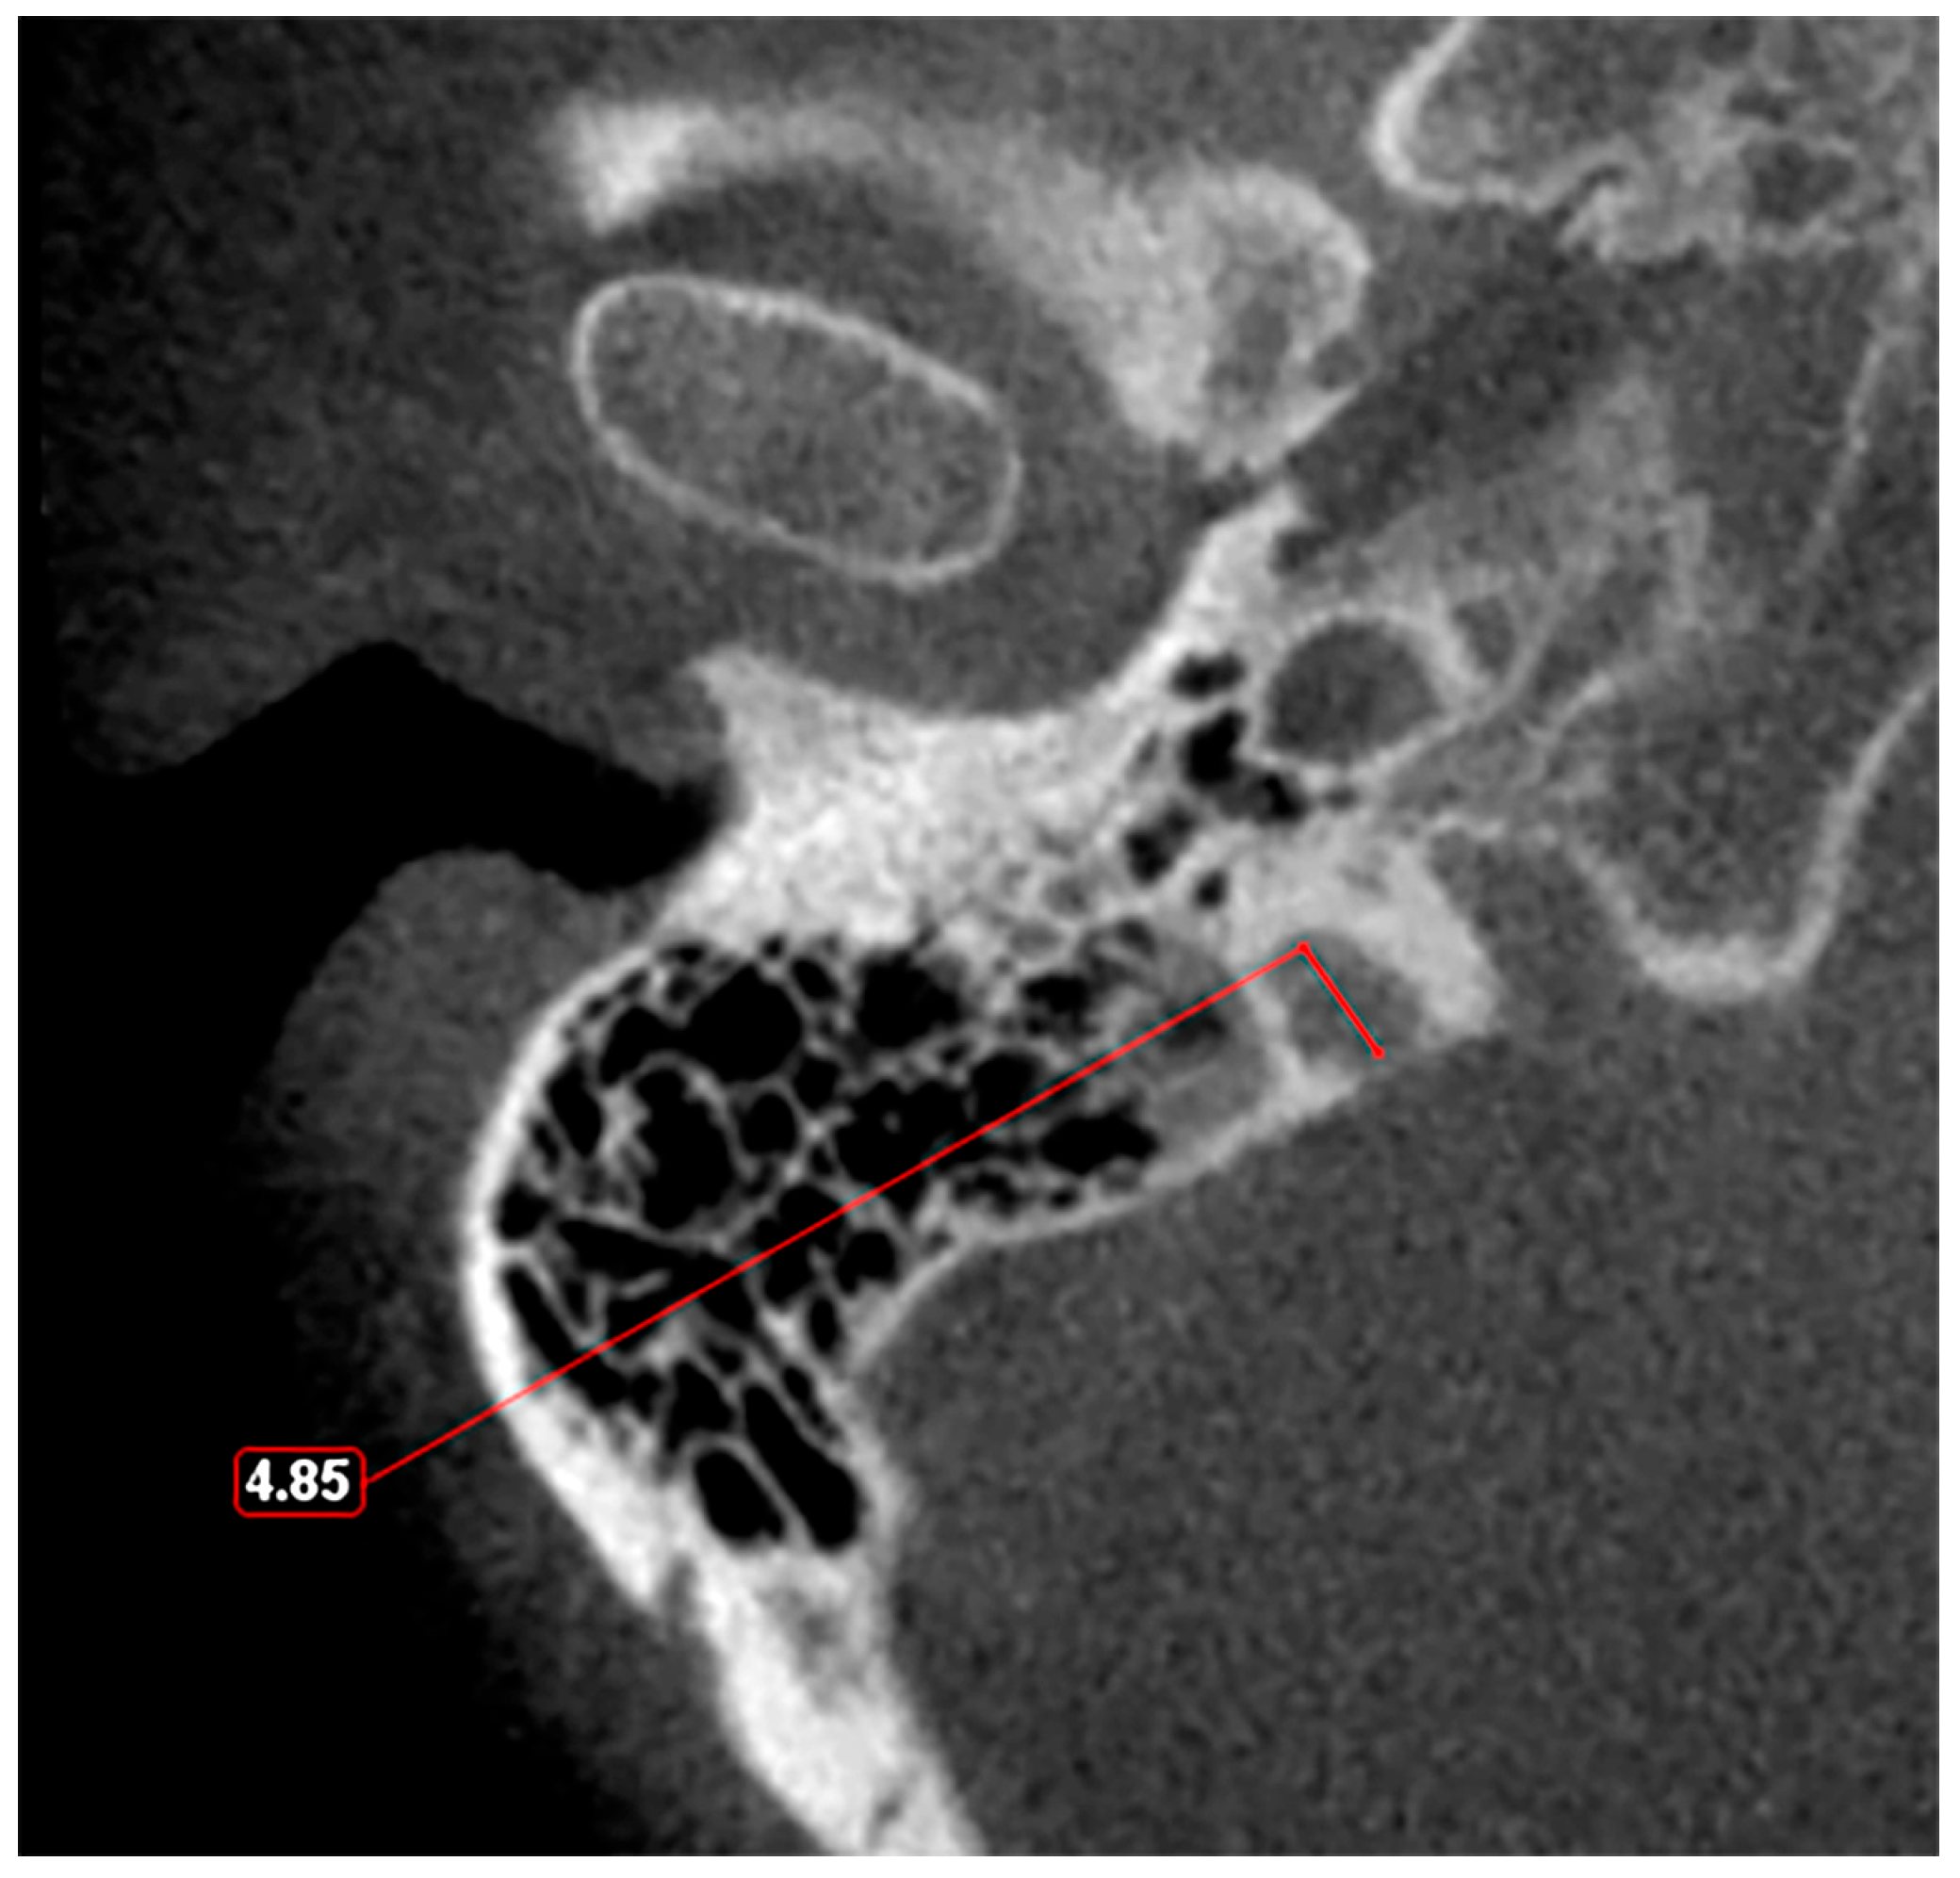

4. High Jugular Bulb

| Roche et al. [49] | JB dome less than 6.5 mm below IAC | CT | 25 |